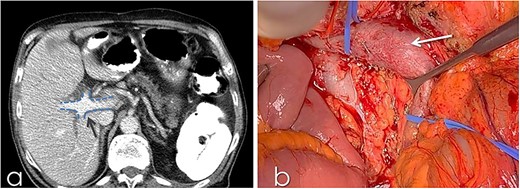

An 82-year-old Caucasian male was diagnosed with obstructive jaundice due to pancreatic duct adenocarcinoma. Computer tomography (CT) and magnetic resonance imaging (Figs 1 and 2) revealed a resectable tumor of the head of the pancreas, a duplicated IVC and a PV trifurcation. The two common iliac veins did not join together at lumbar 4 (L4) vertebra level but ascended separately along the celiac aorta, representing right and left IVC. Specifically, the right external and internal iliac veins joined, forming the right common iliac vein that ran along the abdominal aorta, representing the right IVC. The left IVC formed exactly like the right one while draining to the left renal vein (Fig. 1). This variation can be characterised as ‘type 2a’ in accordance with the classification shown in Fig. 3 (type 2a). Moreover, in our patient, a Whipple procedure was performed without post-operative complications.

(a) CT with contrast demonstrating the trifurcated portal vein (arrow); (b) gross appearance of the duplicated IVC intraoperatively (arrow).